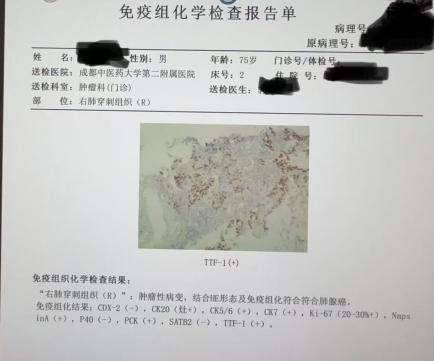

张大爷因消化系统疾患就诊于我院,在后续进一步检查中,发现肺部存在高危结节,考虑为早期肺癌。由于患者高龄,心肺功能差,且合并多种慢性基础疾病,传统手术创伤大、风险高使家属和患者一度束手无策,治疗陷入困境。经我院肿瘤科团队综合评估患者身体状况、肿瘤位置及大小,最终确定采用CT引导下肺结节活检+同步射频消融的个体化治疗方案。

手术当天,在CT引导下,肿瘤科郭医生精准操作,采取同轴活检针精准取样送检,同时将一根直径仅1.3毫米的射频消融针经皮穿刺至肿瘤核心区域。针尖发射高频电磁波,迅速产生高温,使肿瘤细胞凝固性坏死,实现“就地灭活”;一次操作即完成诊断与治疗,做到诊疗一体化。整个手术历时40分钟,其中消融时间仅15分钟。术中患者意识清醒,仅局部麻醉即可耐受,体表仅留下不足2毫米的针眼创口,几乎无疤痕。